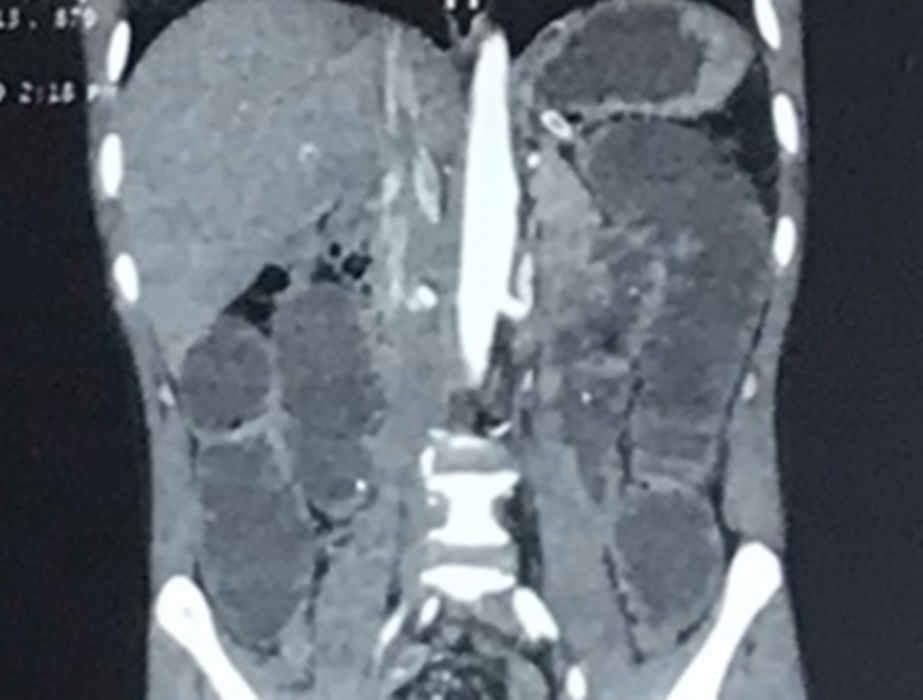

Hình ảnh phim chụp đoạn ruột bị tắc của bệnh nhân. (Ảnh: BVCC)

Quá trình mổ kiểm tra thấy ruột non của bệnh nhân bị dãn to, có khối bã thức ăn dài khoảng 15cm, có nhiều xương cá nhỏ găm từ giữa ruột vào thành ruột, gây tắc hoàn toàn lòng ruột.